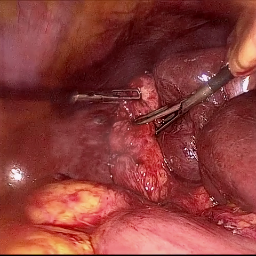

Refer to caption (a) Input Refer to caption (b) DIACMPN Refer to caption (c) Desmoke-LAP Refer to caption (d) PFAN Refer to caption (e) MITNET Refer to caption (f) Salazar Refer to caption (g) Dehamer Refer to caption (h) Ours Refer to caption (i) Target

Figure 2: Comparison of different methods on the DesmokeData dataset.

IV-C2 Qualitative Analysis

Figures 3 and 2 provide a visual comparison of the desmoking results on challenging images from the test sets. The visual results corroborate our quantitative findings. DCP not only fails to remove the dense smoke but also introduces severe color distortion. CNN-based methods like FFA-Net and MSBDN successfully remove a large portion of the smoke but tend to either leave behind a thin layer of residual haze or over-smooth the image, losing critical textural details of the tissue and surgical instruments. The Transformer-based methods, DehazeFormer and PFAN, produce significantly better results by restoring more details. However, they can sometimes struggle with non-uniform smoke distribution, resulting in regions with unnatural brightness or minor artifacts.

In stark contrast, our RGA-Net generates visually superior results that are remarkably close to the ground-truth images. It effectively removes even the densest plumes of smoke while simultaneously preserving fine-grained details, such as blood vessels, tissue textures, and reflections on surgical tools. Furthermore, the color and illumination of the restored scene appear more natural and consistent, which is a direct benefit of our model’s ability to handle both local and global features through its hybrid attention and cross-gating mechanisms. This enhanced visual clarity is crucial for improving the surgeon-robot interface in real-world clinical applications.